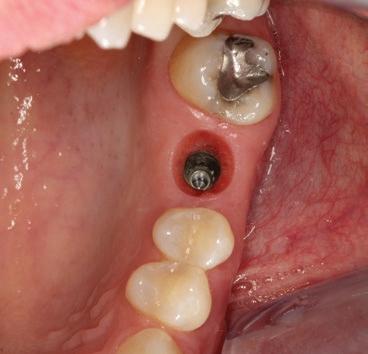

Cette formation de deux jours a pour objectif de vous permettre de diagnostiquer, planifier et réaliser des restaurations implantaires, tant unitaires qu’en édentation partielle fixe impliquant deux implants ou plus. Le contenu aborde les fondements essentiels de la restauration sur implant, ainsi que des notions plus avancées en implantologie prothétique.

Vous verrez l’ensemble des étapes cliniques — de la planification au suivi post-insertion — dans le but d’obtenir des restaurations fonctionnelles, esthétiques et durables. Vous aurez également l’opportunité d’observer des cas cliniques en direct, tant chirurgicaux que prothétiques, réalisés sur des patients, depuis la salle de cours ou la salle de traitement grâce à une retransmission vidéo en temps réel.

Gestion du complexe mucco-gingival et pontique ovoïde

Modification du profil d’émergence pour un contour gingival optimal